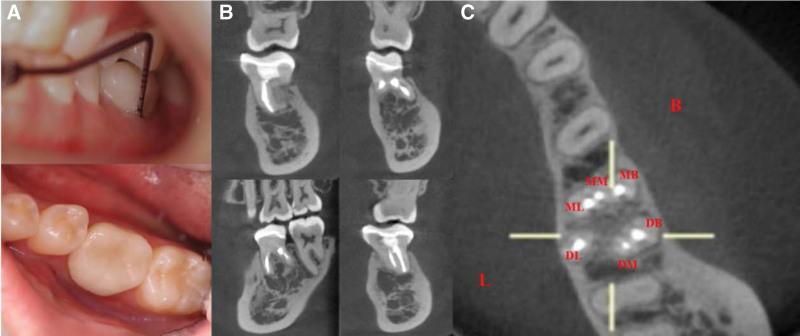

This article presents the clinical report and successful root canal treatment of a 24-year-old healthy female patient with an extensive periapical lesion in a 6-canal first mandibular molar. The patient was admitted to the endodontic department because of a periapical abscess found 1 month ago in her left mandibular first molar.

Chronic apical periodontitis was diagnosed based on clinical examination coupled with radiographic and cone-beam computed tomography images.

The treatment plan was to first perform root canal therapy and then perform clinical observation.

During 1-year follow-up period, the treated tooth was asymptomatic, and complete resolution of the extensive apical lesion was eventually achieved, as shown in the postoperative cone-beam computed tomography images and clinical examination.

The present case emphasizes the importance of a comprehensive understanding of root canal morphology, especially rare anatomical variations, to ensure successful root canal treatment. Additionally, the case report adds to the library of previously reported cases of extensive periapical lesions with a direct connection to the root canal system, which demonstrates the potential clinical advantages of root canal therapy as a conservative nonsurgical approach in these cases.